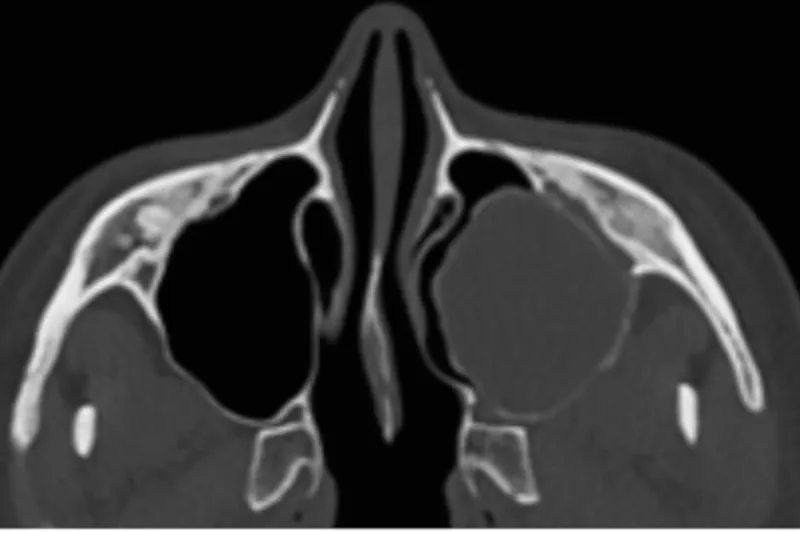

En 28-årig kvinde blev henvist fra egen tandlæge til Tand-, Mund- og Kæbekirurgisk Afdeling, Aarhus Universitetshospital, for fjernelse af cystelignende forandring i sinus maxillaris.

Ved røntgenundersøgelse fandtes en større cystelignende radiolucent forandring og en displacering af +8.

Der blev i generel anæstesi foretaget biopsi af den cystelignende forandring samt fjernelse af +7 og +8. Den histopatologiske undersøgelse viste, at det var et unicystisk ameloblastom og en follikulær cyste.